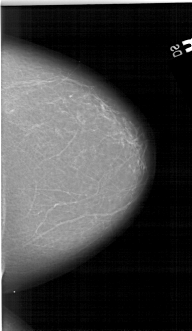

A_1275_1.LEFT_MLO

LEFT_MLO LINES 6601 PIXELS_PER_LINE 4231 BITS_PER_PIXEL 12 RESOLUTION 43.5 OVERLAY